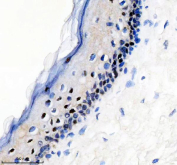

Immunohistochemical staining of FFPE human skin cancer tissue with phospho-c-Myc antibody, HRP-secondary and DAB substrate. HIER: boil tissue sections in pH8 EDTA for 20 min and allow to cool before testing.